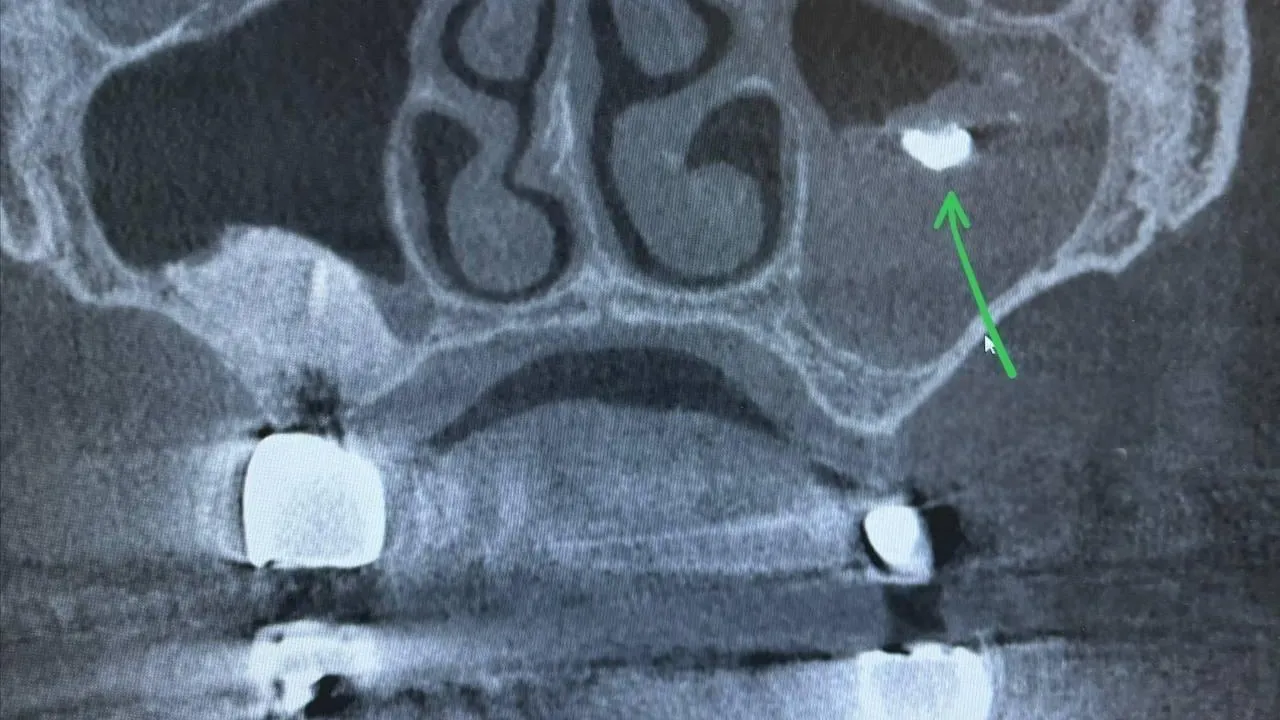

Женщина в возрасте 45 лет обратилась в больницу в Видном с жалобами на боли в левой щеке, выделения из носа и неприятное ощущение стекания жидкости по задней стенке глотки. Компьютерная томография помогла обнаружить инородное тело в верхнечелюстной пазухе. Им оказался фрагмент пломбы, который стал очагом развития патогенных микроорганизмов.

Как рассказал врач-оториноларинолог Видновской клинической больницы Магомед Гасанов, в ходе диагностики у пациентки выявили мицетомы — скопления грибковых масс внутри пазухи. Ее причиной стал пломбировочный материал.